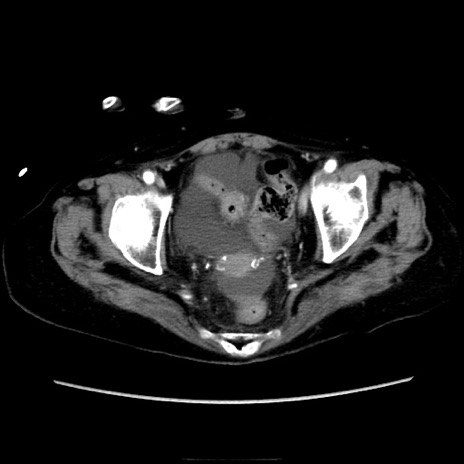

症例40(横断像)

【症例】90歳代女性

【主訴】腹痛・嘔吐

【現病歴】 食欲低下、嘔吐があり昨日他院受診。肺炎と診断され入院となる。入院後より腹部全体に圧痛あり。胃管留置され経過みていたが、症状持続するため、

当院転院となる。

【既往歴】胸椎圧迫骨折、胆石症

【身体所見】腹部:中央に激痛あり、圧痛あり、反跳痛不明

【データ】WBC 17100、CRP 18.82

横断像